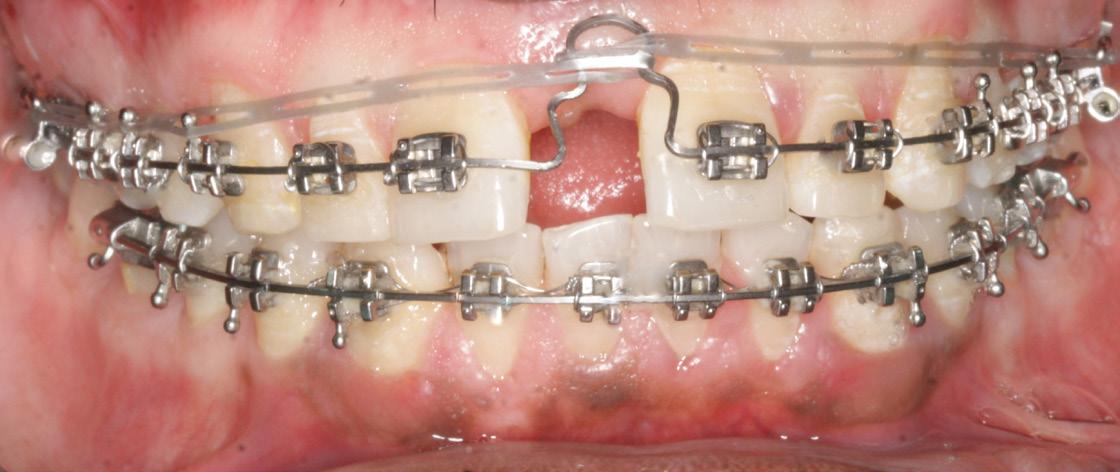

• Achieve Class I molar and canine relationship

• Enhance facial esthetics

Treatment plan

• Myofunctional appliance therapy to restrict the maxillary growth and advance the mandible

• Using Pre-adjusted edgewise appliance 0.022 slot Roth prescription -Leveling and alignment

• Retention plan – Upper and lower removable retainers.

Cervical pull headgear was given to patient for 12- 14 hour wear per day using molar band. (Figure 5)

Then, a maxillary anterior bite plate with groovings in the anterior palatal region was given for another 6 months to maintain and retain the skeletal corrections.

Post-retention occlusion before the start of fixed orthodontic appliance

During the retention period, the posterior open bite decreased and the occlusion got almost settled (Figs. 7 and 8).

Figure 3: Radiographic Findings

Figure 4: Visual treatment objective was positive

Figure 5: Pahase 1: Cervical pull headgear

Twin Block Twin block appliance was placed for 8 months. (Figure 6)

Figure 6: Phase 2, twin block appliance

Figure 7: Extraoral

Figure 8: Intraoral

Phase II fixed appliance

•Treatment Roth prescription 022 slot pre-adjusted edgewise appliance

• Alignment was carried out using round Niti wire. Wire size was progressively increased to 017 -025 inch in both maxillary and mandibular arches and then using 019 - 025